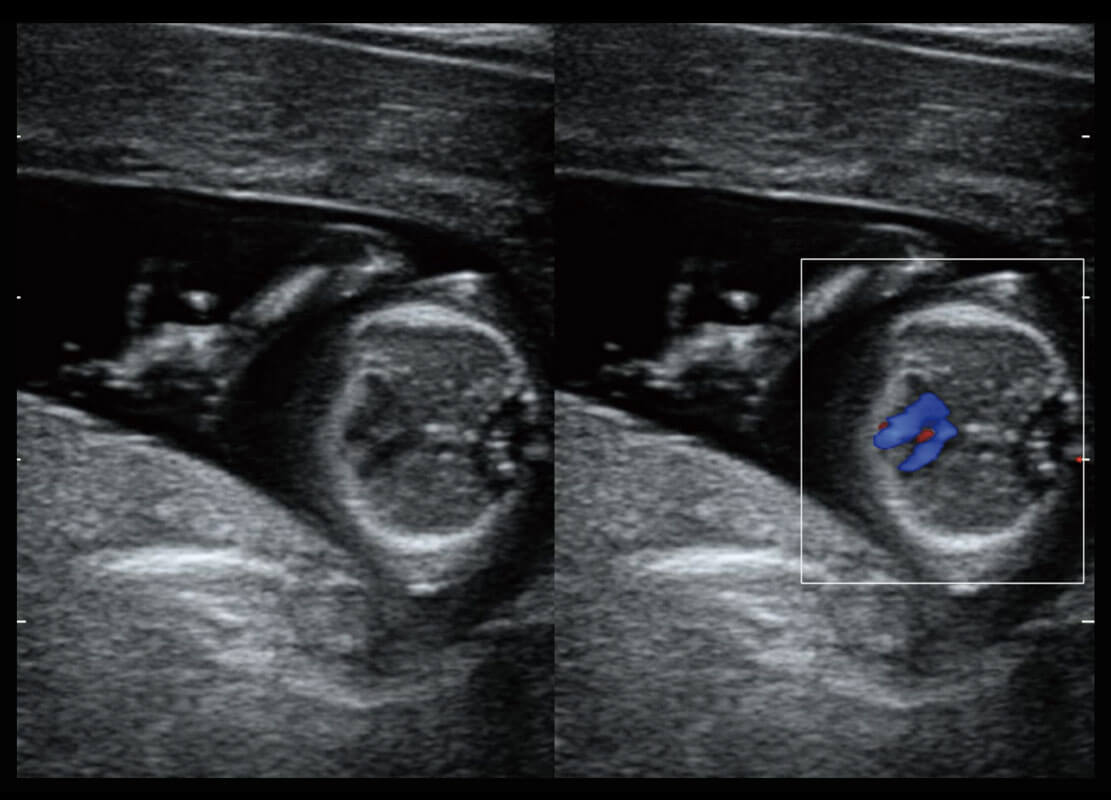

P60搭载一系列胎儿心脏成像技术,实现精细的胎儿心脏评估。

四腔心血流